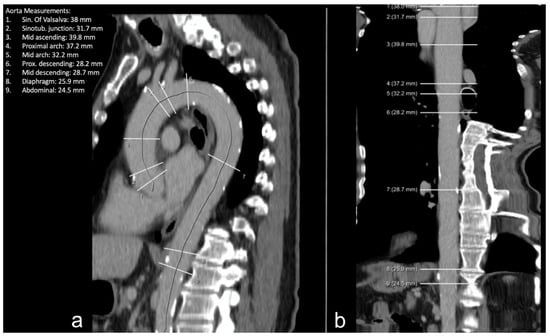

Figure 3.

Example of the thoracic aorta imaged via CT in plane reformatted along the center line (a) and straightened reconstruction (b). White lines: measurement planes of the diameter at each dedicated location.